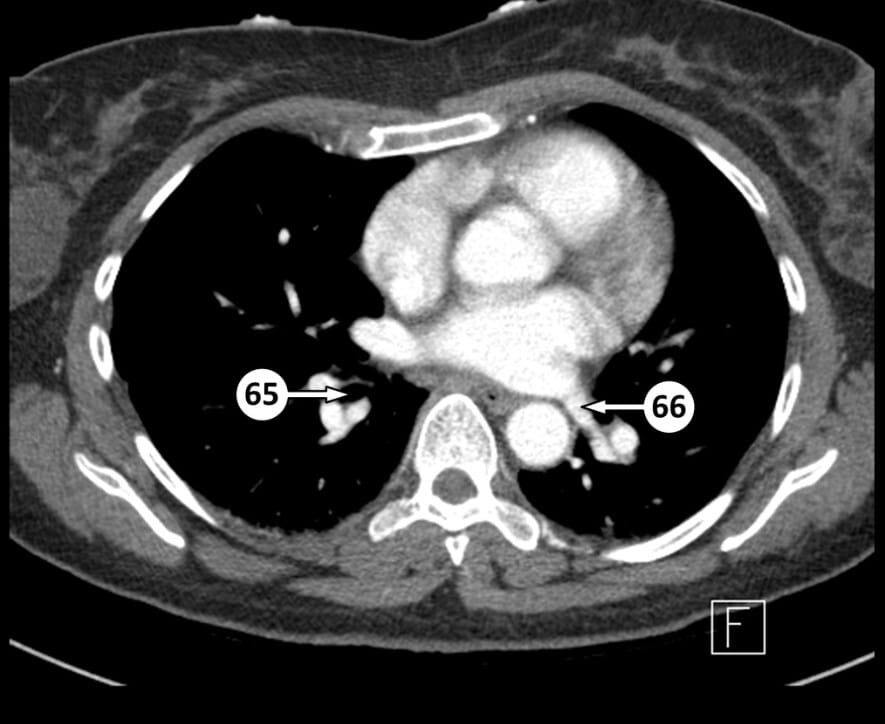

65. right inferior lobe bronchus

66. left inferior pulmonary vein